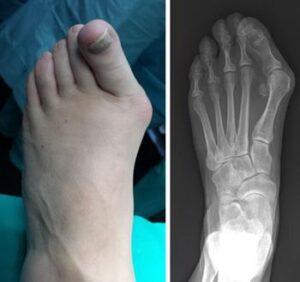

- Chronic Inflammation and Swelling: Persistent big toe inflammation that does not respond to rest or medication.

- Toe Deformity: Noticeable drifting of the big toe toward the smaller toes, sometimes causing the toes to overlap or cross.

You may require several preoperative tests, including blood counts, an echocardiogram, and a chest X-ray. You may also need to provide a urine sample.To help plan your procedure, your doctor may order special foot X-rays. These X-rays should be taken in a standing, weightbearing position to ensure your doctor can clearly see the deformity in the foot. These special X-rays assist your doctor in making decisions about where along the bone to perform an osteotomy to provide enough corrective power to straighten the toe.

For many individuals with bunions, simple measures such as wearing wider shoes or using shoe pads can effectively reduce pressure on the big toe and provide pain relief. However, when these conservative treatments fail to alleviate symptoms, your doctor may recommend bunion surgery. Bunion surgery aims to correct the misalignment of the big toe by realigning the affected bones. There are several surgical techniques available, and the choice of procedure depends on the severity of the bunion and your specific needs.Are You a Candidate for Bunion Surgery?